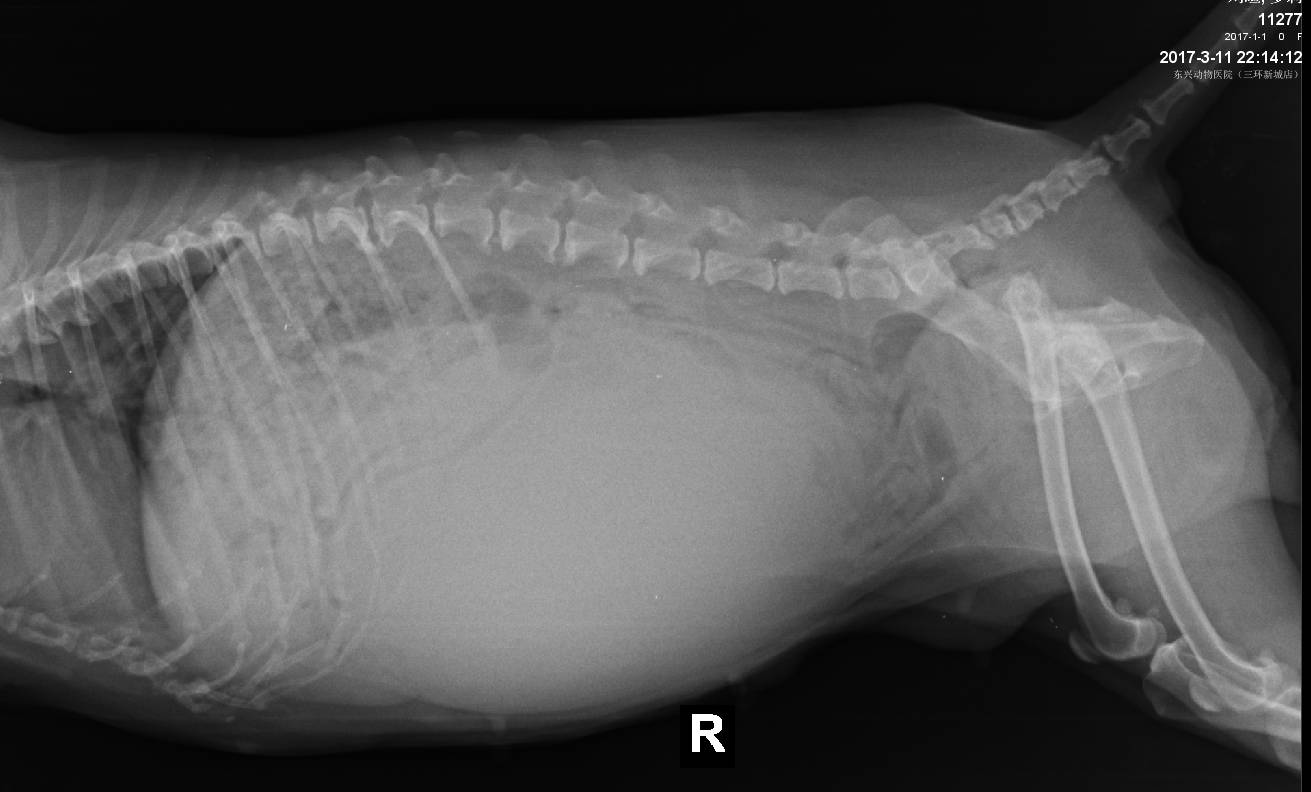

经过实验室及影像学检查,查找发病原因及体况评估:

根据临床检查结合实验室影像检查结果分析:

a疑似左侧肾脏囊肿,卵巢囊肿,乳腺肿瘤,重度牙结石,肺脏情况尚可,心脏肥大,阴道增生,血液学结果尚可,凝血机制尚可

初步诊断:疑似左侧肾脏囊肿(肿瘤?),乳腺肿块(肿瘤?)卵巢囊肿(肿瘤?),阴道增生,白内障。

常规术前准备,一级疼痛管理,麻醉管理,常规手术开腹后发现左肾囊肿性病变,增大,右肾尚可,双侧卵巢囊肿,经过分离结扎,摘除了病变囊肿及子宫卵巢,之后行双侧乳腺全切术。手术时间进行3.5小时,术中麻醉疼痛管理,狗狗体征相对稳定。